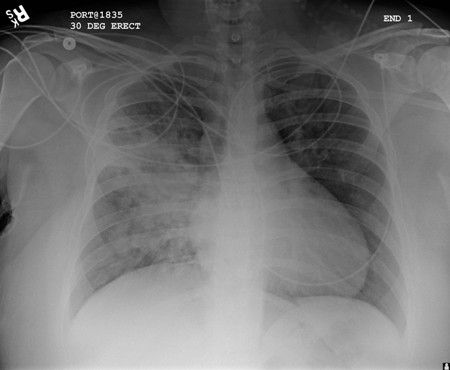

A. Radiografía portátil de tórax en posición erguida antes de la aspiración; B. Radiografía de tórax 1 hora después de la aspiración, en la que se muestran infiltrados alveolares difusos bilaterales, peores en las bases del lado derecho

De la colección personal del Dr. S. Murgu y el Dr. H. Colt, University of California en Irvine Medical Center